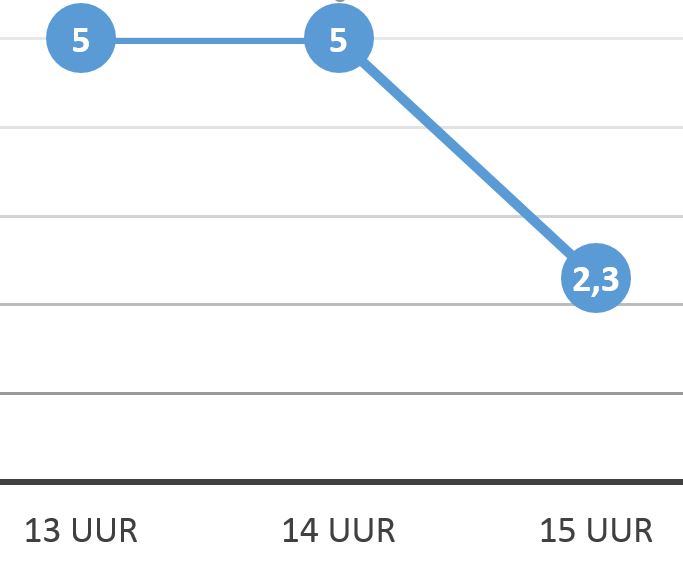

Wanneer een patiënt terugkomt van een operatie is het belangrijk met een verpleegkundige diagnose te benadrukken welke complicaties zich kunnen voordoen, bijvoorbeeld shock. Het zorgresultaat geeft hiervoor relevante indicatoren weer. Door deze indicatoren te scoren kun je de data in een grafiek weergeven (5 = best mogelijke score, 1= slechtst mogelijke score).